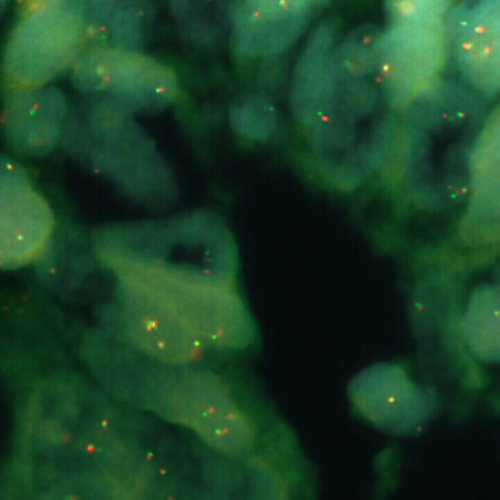

FUS (16p11.2) Break probe hybridized to liposarcoma material.

The fused in sarcoma (FUS) gene was originally shown to be rearranged in myxoid liposarcomas harboring a t(12;16)(q13;p11) translocation. FUS has also been shown to be involved in other recombinations: with ERG in acute myeloid leukemia carrying a t(16;21), with ATF1 in band 12q13 in angiomatoid fibrous histiocytoma, and with CREB3L2 in fibromyxoid sarcoma. A break or split probe for FUS is best used to analyze translocation of the FUS (16p11) gene on formalin fixed paraffin embedded tissue for routine clinical diagnosis. The FUS (16p11) Break probe is optimized to detect translocations involving the FUS gene region at 16p11 in a dual-color, split assay on metaphase/interphase spreads and paraffin embedded tissue sections.